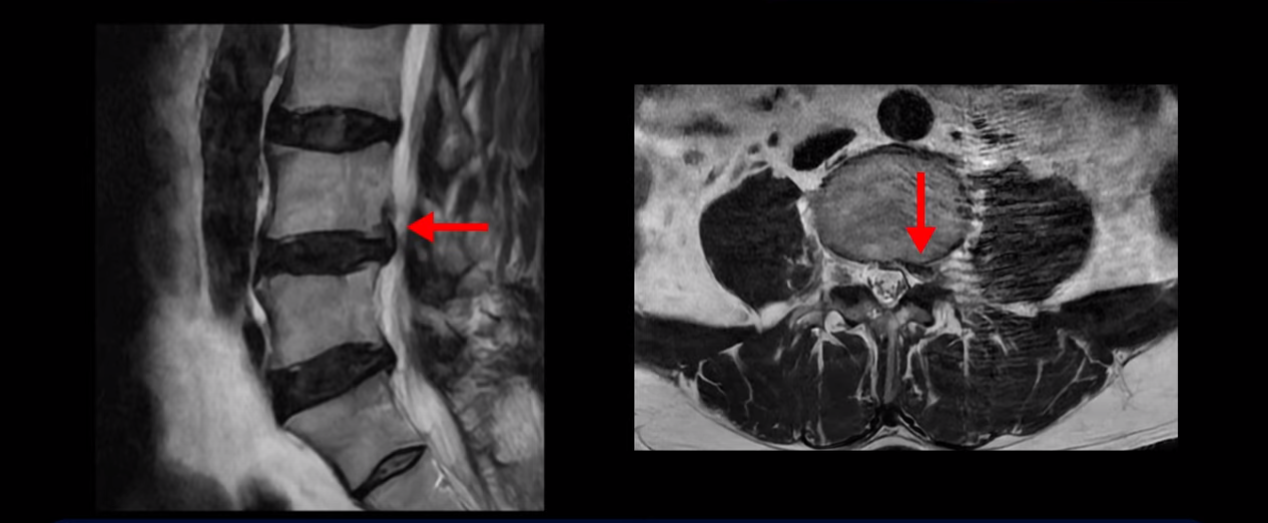

이분은 왼쪽 무릎 아래로 본인 표현으로는 다리를 잘라 버리고 싶다고 할 정도의 심한 통증이 있는데 보통 이런 표현은 디스크 파열이 발생했을 때 많이 사용하는 표현입니다. 이분 4번 5번 디스크를 자세히 보면 왼쪽으로 파열되어 밀려 올라간 디스크 수핵을 볼 수 있습니다.

옆에서도 보이지만 단면에서도 왼쪽으로 심하게 밀려나온 수핵이 잘 보입니다.